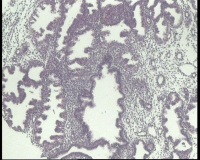

| 图片: | |

- 急!请老师看看34岁子宫内膜

| 性别 | 女 | 年龄 | 34岁 | 临床诊断 | 子宫内膜息肉? |

| 一般病史 | 末次月经:11月20日,近两个月无诱因性生活有阴道少许血性分泌物 | ||||

| 标本名称 | 宫内容物 | ||||

| 大体所见 | 膜样碎组织3.0厘米 | ||||